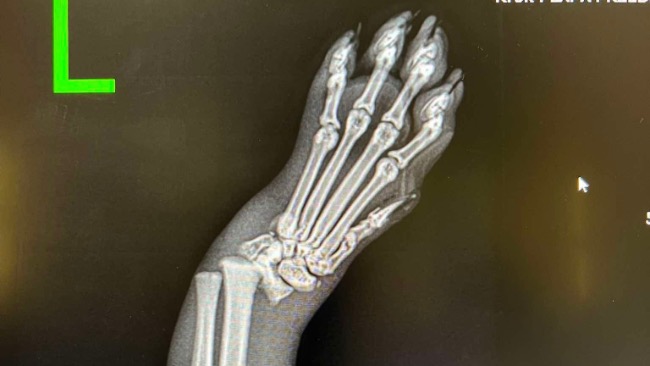

Moja opieka nad Cizią rozpoczęła się w dniu, w którym jej właścicielka z niej zrezygnowała. Kotka uległa wypadkowi, w skutek którego konieczna była amputacja lewej przedniej łapki. Dotychczasowa właścicielka Cizi nie podjęła się dalszej opieki nad nią, tym samym kotka poszukiwała nowego domu.